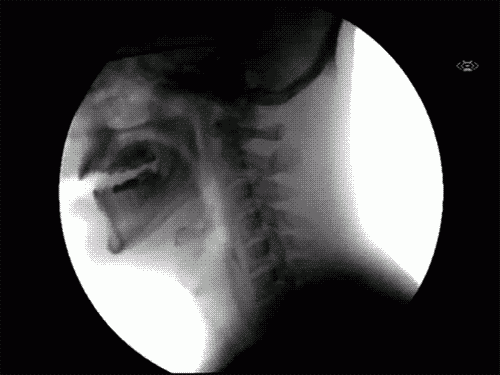

Ez történik, amikor nyelünk